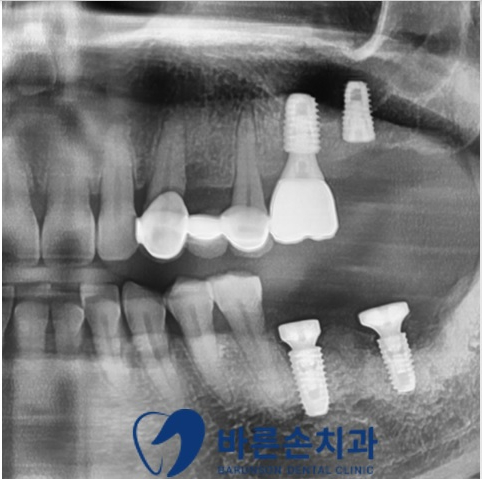

통증을 유발했던 치아를 모두 발치하고 염증도 깨끗하게 제거합니다.

그 다음, 그 날 바로 임플란트 식립을 합니다.

위에는 상악동 거상술,

아래는 골이식을 동반한 임플란트 식립을 했습니다.